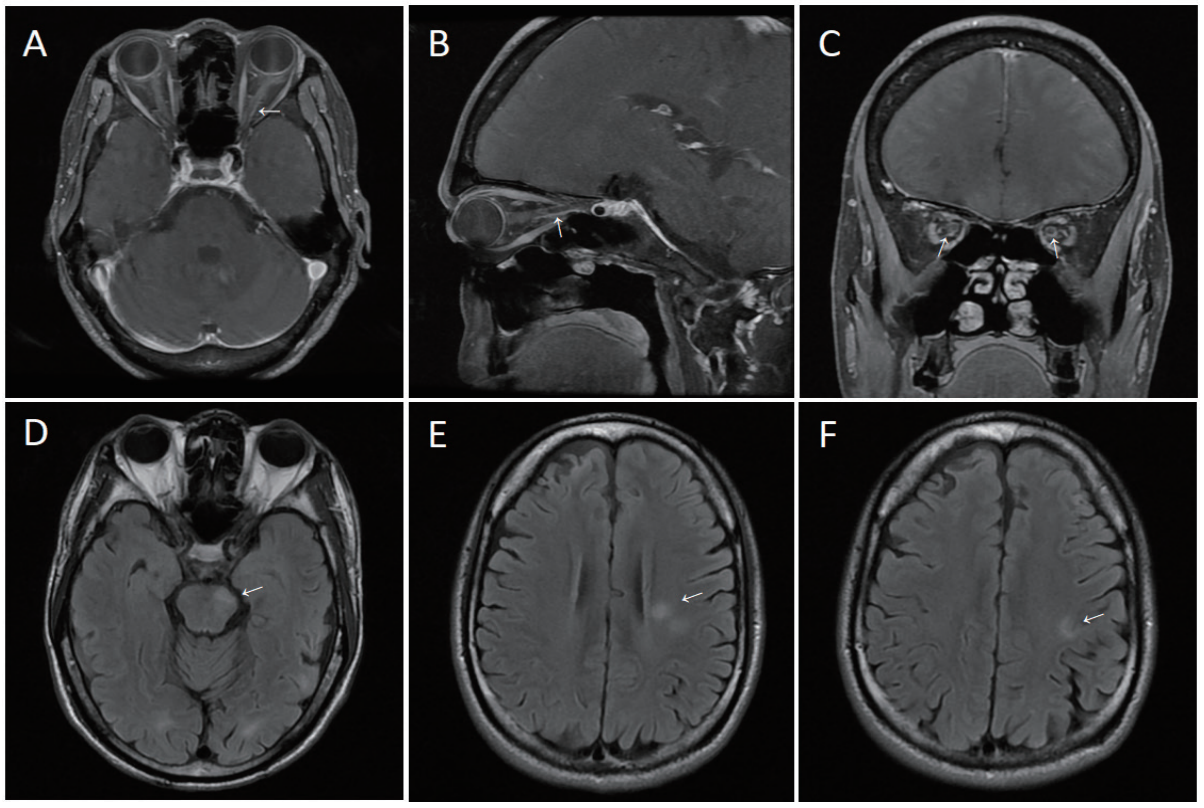

颅脑MRI表现为视神经信号异常及增强3例,皮层及皮质下白质病变2例,脑干病变3例,软脑膜病变1例。VEP异常4例,主要表现为潜伏期延长和(或)波幅降低(图1)。脑电图异常4例,主要表现为癫痫样放电或局部慢波活动。

图 1 影像学表现

Figure 1 Imaging findings

A-C demonstrate orbital T1-weighted contrast-enhanced sequences of Patient 1, revealing left optic nerve atrophy with linear contrast enhancement within the proximal segments of bilateral optic nerves (arrows); D-F show brain T2 FLAIR sequences of Patient 4, demonstrating multifocal hyperintense lesions in the left brainstem, left periventricular white matter, and centrum semiovale.